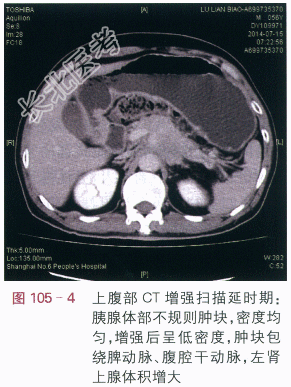

影像学资料如图105-1~图105-4所示。

读片分析:上腹部CT平扫显示胰腺体部增大,密度均匀,尾部萎缩,胰腺周边模糊(见图105-1),增强扫描动脉期:胰腺体部不规则肿块,增强后动脉期呈低密度,肿块边缘不清,肿块包绕脾动脉、腹腔干动脉(见图105-2);门脉期:胰腺体部不规则低密度肿块,肿块包绕脾静脉(见图105-3)。延时期肿块密度呈低密度,肿块包绕腹腔血管、并向周边侵犯,左肾上腺体积增大(见图105-4)。